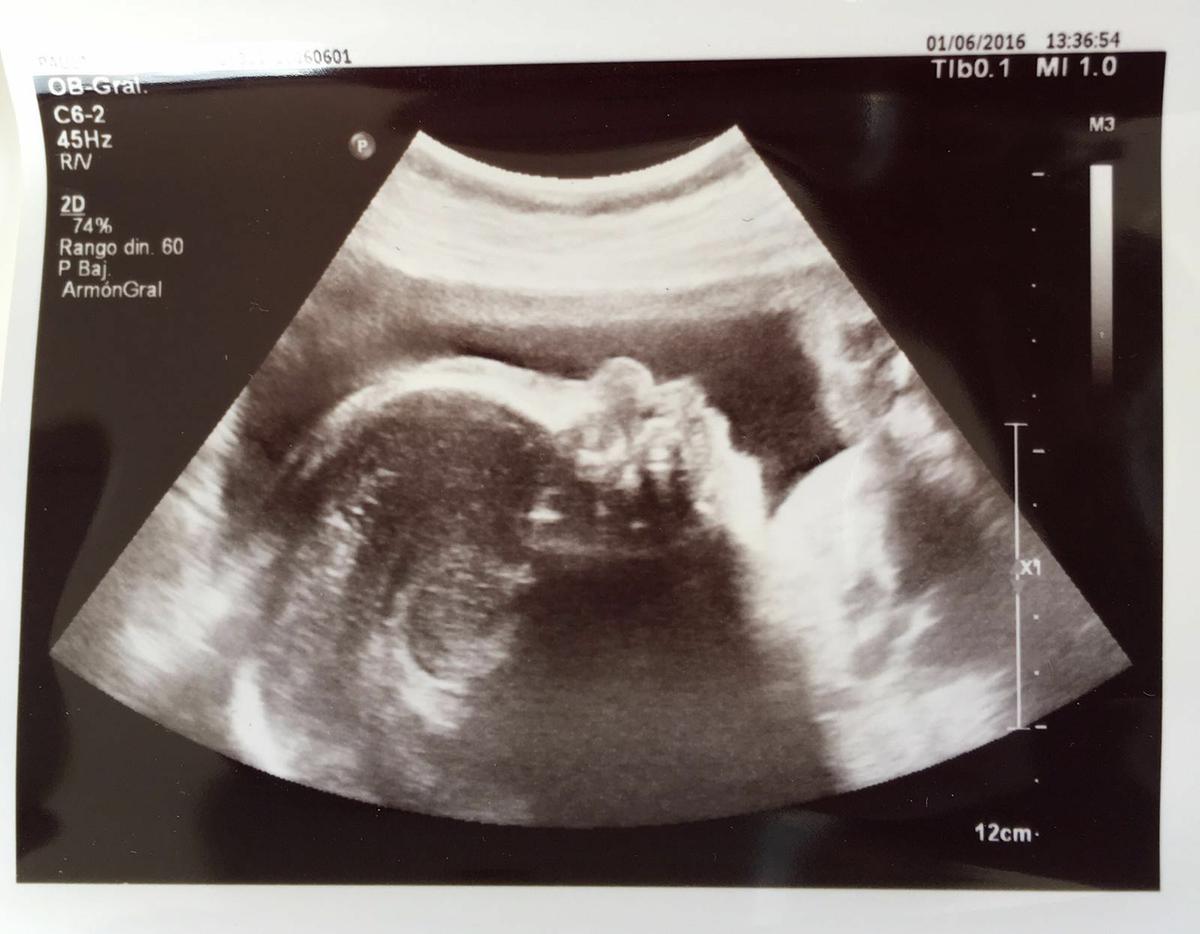

Ayer tuve una nueva ecografía de la semana 30 de embarazo, tanto papi como mami teníamos unas ganas terríbles de ver a la pequeña.

Os voy a enseñar su carita

Parece que esta algo enfadada…jajaja!! Pero ya se le ven las facciones perfectamente, es chatina como sus padres y la boca completamente perfilada.

En esta foto se ve el cordón por delante.

Y esta última es en 2d, las otras eran ecos en 4d que la verdad es que es una pasada…

Mi bichilla pesa 1448gm casi llegamos al kilo y medio, me han dicho que para la semana 30 el peso es el correcto, asi que estamos súper contentos!!!!